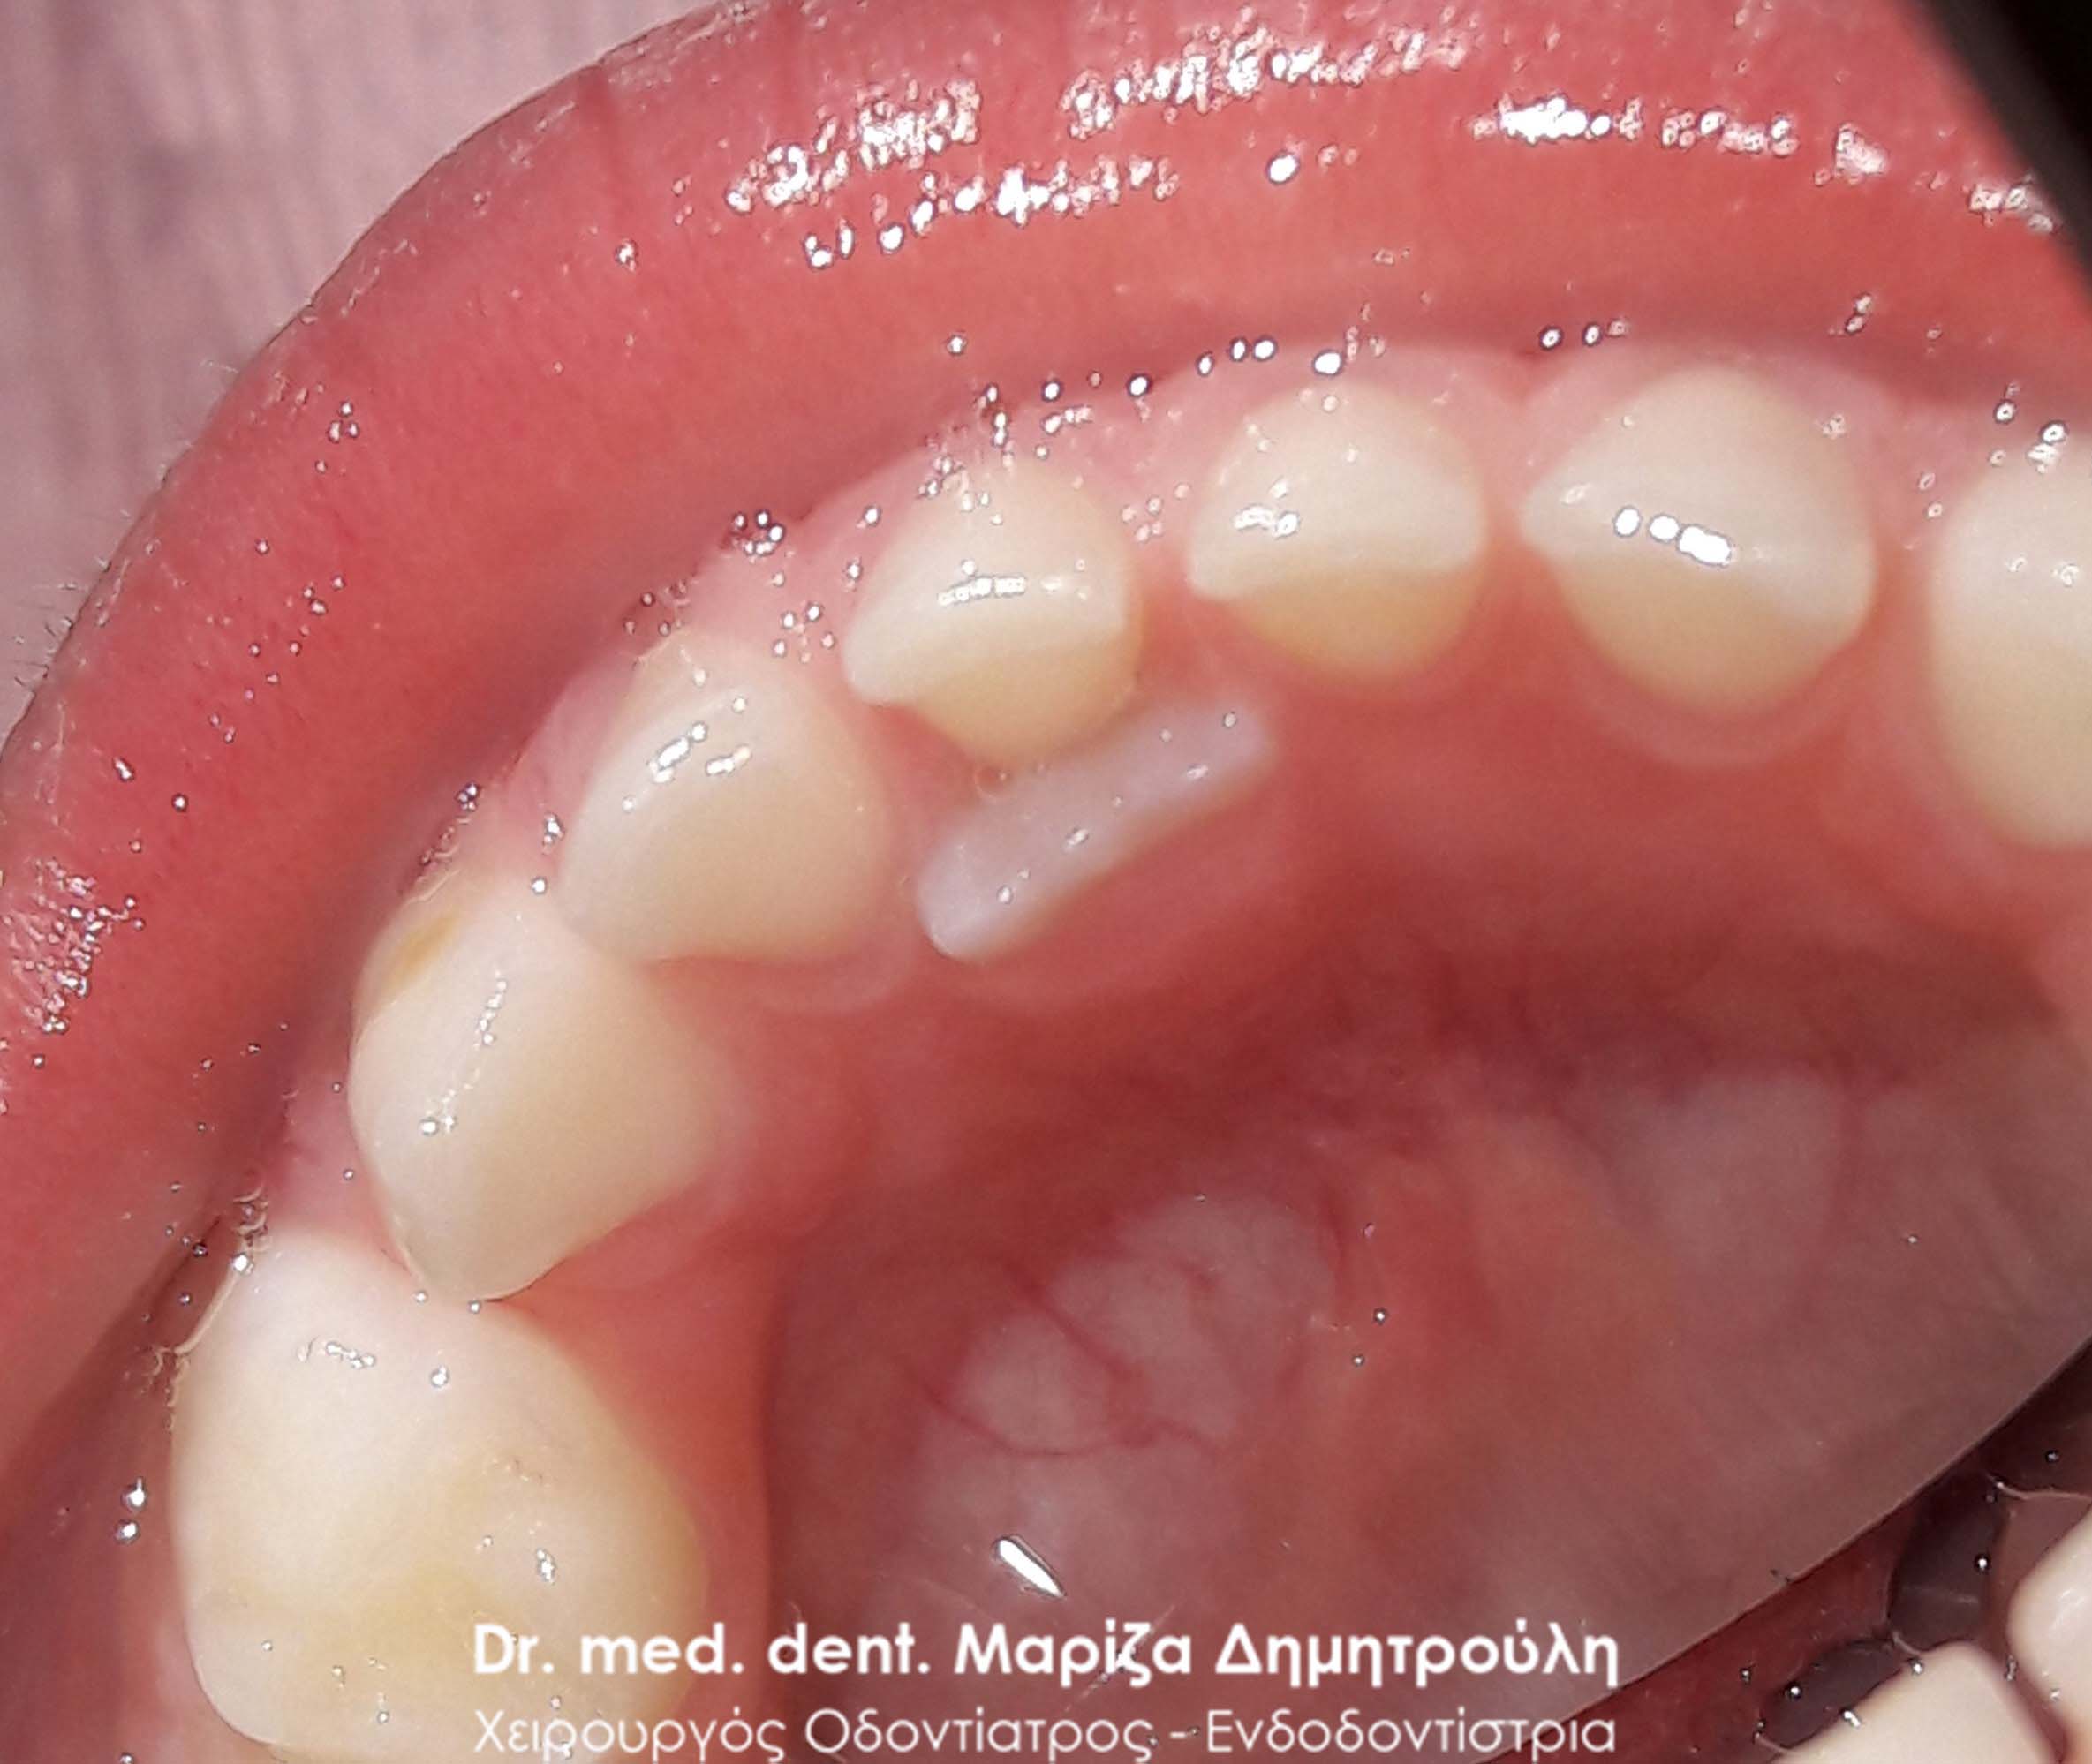

Περιστατικό – Εξαγωγή παιδικού δοντιού (διπλό δόντι / παραμονή νεογιλού δοντιού)

Η μαμά του μικρού νεαρού είχε τρομάξει καθώς τα δοντάκια του παιδιού της τον τελευταίο καιρό παρουσιάζουν την παρακάτω εικόνα που δείχνουν οι φωτογραφίες. Το πρόβλημα βέβαια ήταν πολύ απλό, καθώς για τη λύση του προβλήματος απαιτούταν μόνο η εξαγωγή των παιδικών δοντιών. Στην πραγματικότητα κάτω από τα παιδικά δοντάκια είχαν ήδη ανατείλει τα μόνιμα δόντια, τα οποία πίεζαν από κάτω τα αντίστοιχα παιδικά δοντάκια. Για αυτό το λόγο φαίνεται οι νεογιλοί τομείς να είναι στον αέρα. Το αισθητικό πρόβλημα αντιμετωπίστηκε άμεσα με την εξαγωγή των παιδικών δοντιών.